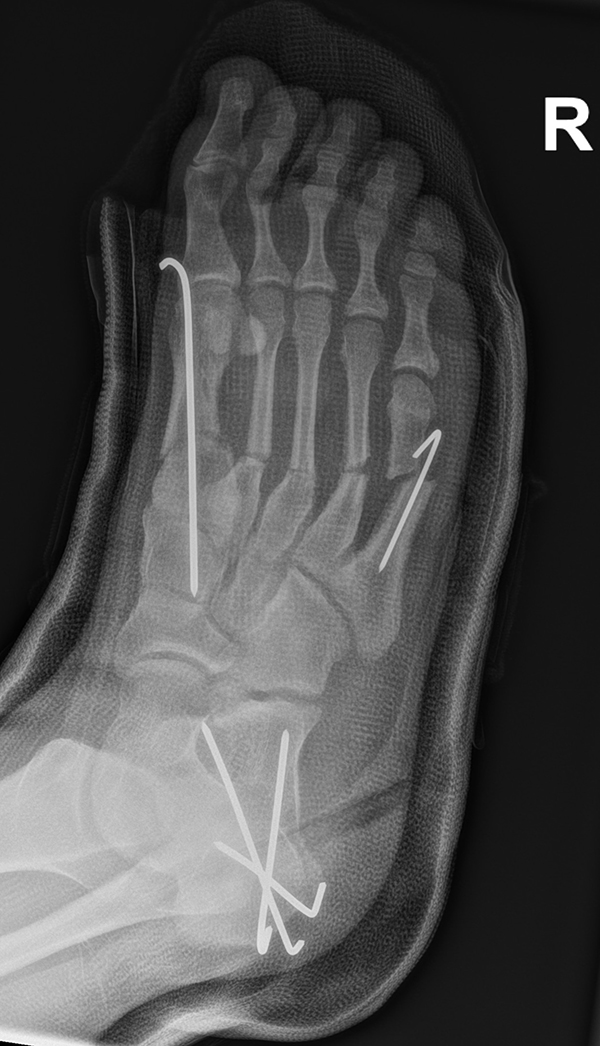

In der Regel bestehen aktive Wachstumsfugen bei Mädchen bis zum 12. und bei Jungen bis zum 14. Lebensjahr, mit Abweichungen von einem Jahr nach unten und nach oben. Präzise Informationen unter anderem darüber gibt das präoperative Röntgenbild (Abb. 2).

Abb. 2 a-c: offene Wachstumsfugen MT I Basis und Zehen (a), teilweise geöffnete Wachstumsfugen (b) und geschlossene Wachstumsfugen (c).

Zum Lesen der Bildbeschreibung und zur Vollansicht bitte die Bilder anklicken. Bilder: A. Helmers.